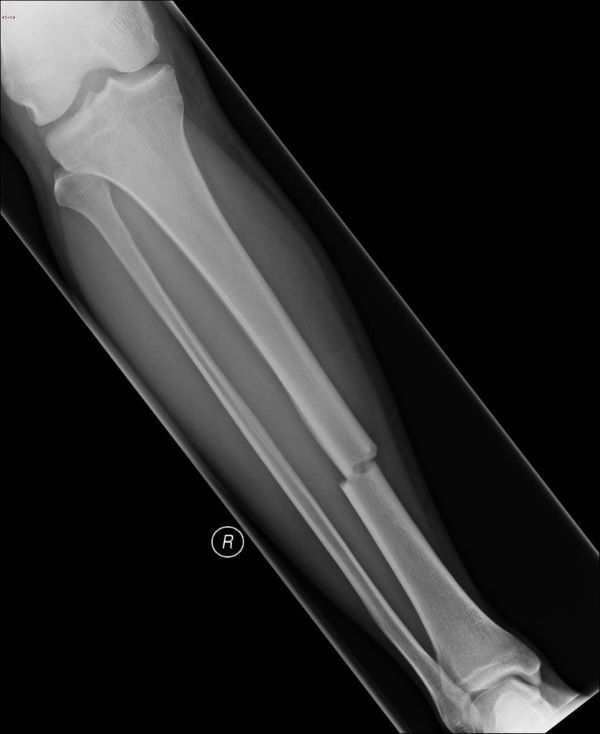

What type of fracture is this?

Transverse

Straight horizontal line through tibia